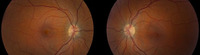

Hipertensão intracraniana idiopática

Atrofia óptica bilateral

Do acervo pessoal do Dr. M. Wall; usado com permissão